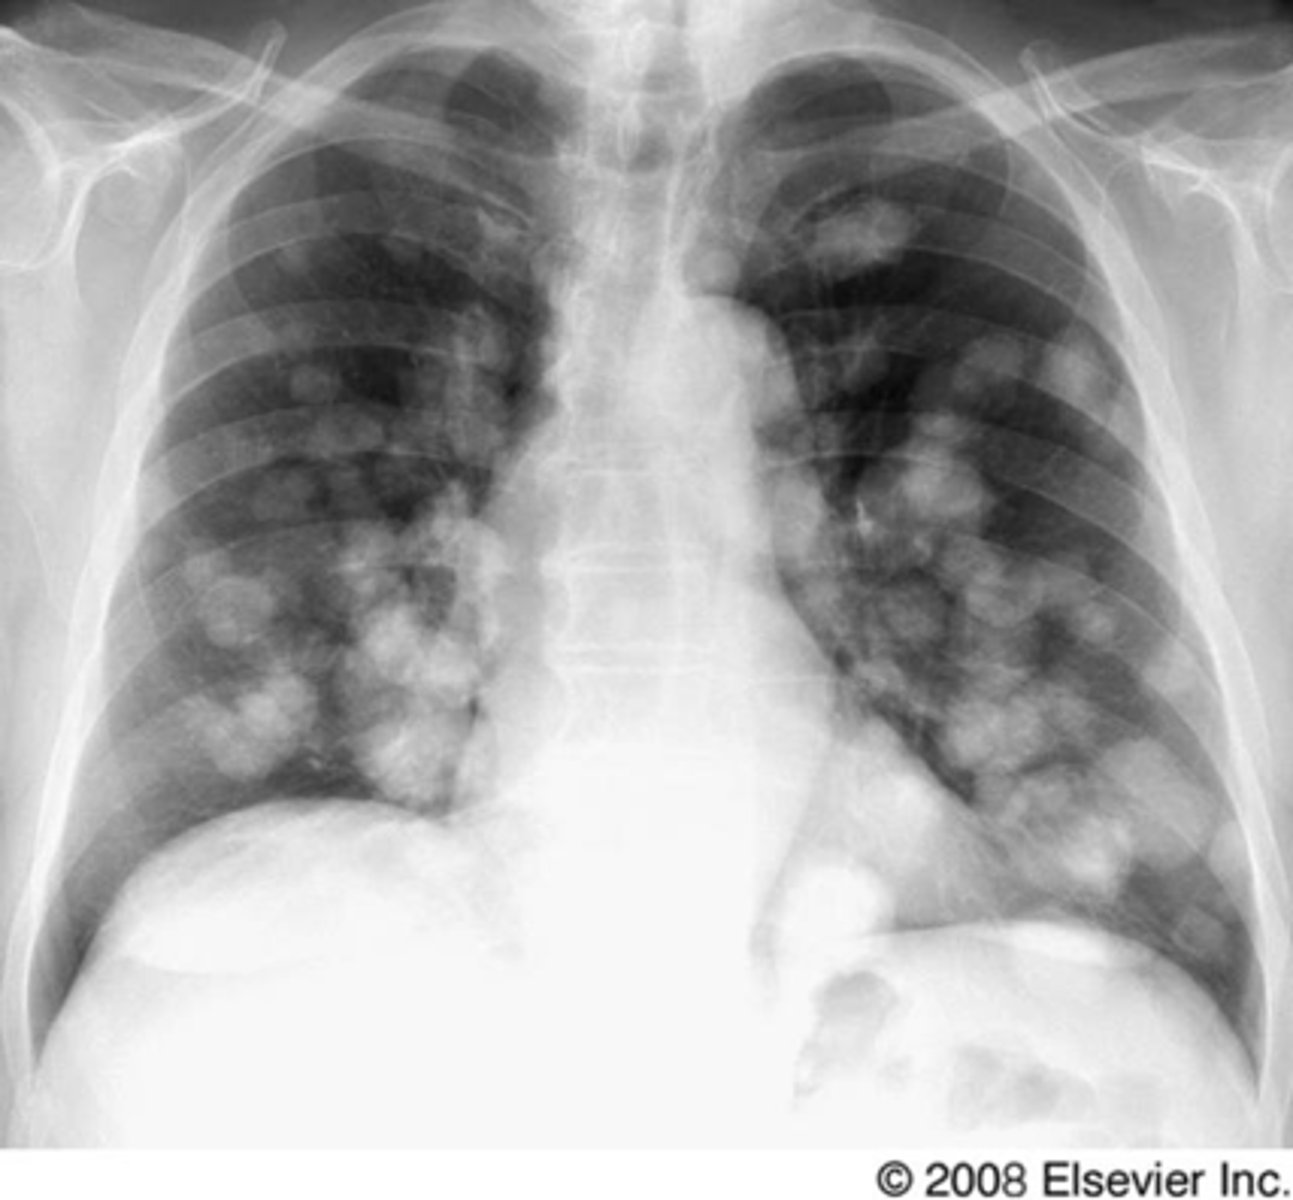

Multiple nodules- metastatic